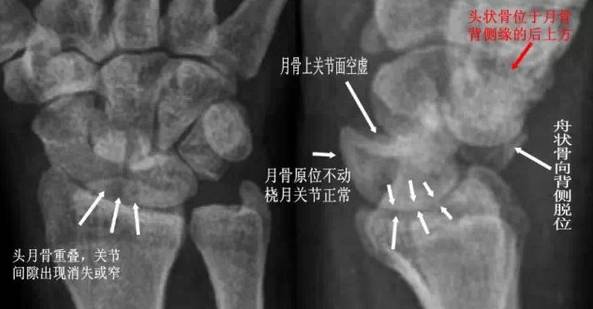

(2) 经舟骨月骨脱位:除月骨脱位外,同时伴有舟骨骨折,且骨折近段随月骨一起向前脱位,骨折远段仍处于原位置。

经舟骨月骨脱位影像特点

(4)经舟骨月骨周围脱位:表现为月骨周围脱位伴舟骨骨折,且骨折远段随头骨向后脱位,而骨折近段与桡骨、月骨关系保持正常。

经舟骨月骨周围脱位影像特点